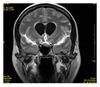

Image contrast is created by differences in the strength of the NMR signal recovered from different locations within the sample. This depends upon the relative density of excited nuclei (usually water protons), on differences in relaxation times (T1, T2, and T*2) of those nuclei after the pulse sequence, and often on other parameters discussed under specialized MR scans. Contrast in most MR images is actually a mixture of all these effects, but careful design of the imaging pulse sequence allows one contrast mechanism to be emphasized while the others are minimized. The ability to choose different contrast mechanisms gives MRI tremendous flexibility. In the brain, T1-weighting causes the nerve connections of white matter to appear white, and the congregations of neurons of gray matter to appear gray, while cerebrospinal fluid (CSF) appears dark. The contrast of white matter, gray matter and cerebrospinal fluid is reversed using T2 or T*2 imaging, whereas proton-density-weighted imaging provides little contrast in healthy subjects. Additionally, functional parameters such as cerebral blood flow (CBF), cerebral blood volume (CBV) or blood oxygenation can affect T1, T2, and T*2 and so can be encoded with suitable pulse sequences.

Normal axial T2-weighted MR image of the brain.jpg